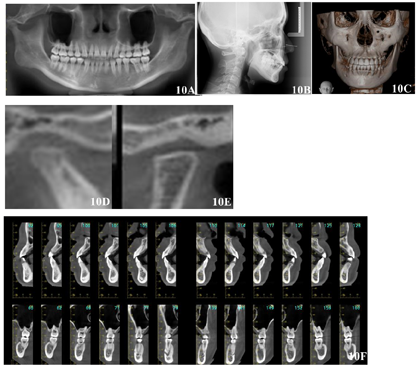

(5)正畸术前X线检查:自然头位下,曲面断层X线片未见明显牙槽骨吸收,未见18、28、38、48。头颅三维重建可见颏部明显右偏。CBCT显示左侧髁突术后断面平整,关节间隙增大;右侧髁突形态不佳,骨皮质连续,关节前、上、后间隙约为1:1:2;各牙根-骨关系未见明显异常。头颅侧位X线片测量数据:SNA角81.8°,SNB角80.6°,ANB角1.2°,FH-MP角36.9°,PP-GoGn角29.8°(图3,表1)。

该患者矫治时间共29个月,矫治后患者自然状态下左右面部基本对称,颏部无明显偏斜,面下1/3高度减小,相貌趋向直面型,颏部肌肉放松。口内检查显示,前牙达到正常覆合覆盖,双侧尖磨牙I类咬合关系,上下中线齐,上下牙弓均呈光滑卵圆形,患者具有前牙和尖牙保护合。曲面断层X线片显示矫治后各牙牙根平行度尚可,未见明显牙根及牙槽骨吸收。CBCT显示左侧关节间隙减小,双侧髁突骨皮质连续;各牙根尖均位于松质骨内。矫治后头颅侧位X线片显示:SNA角80.5°,SNB角78.6°,ANB角1.9°,FH-MP角35.0°,PP-GoGn角29.4°,矫治后FH-MP角较术前减小1.9°。矫治前后头颅侧位片X线片重叠图显示下颌稍有逆时针旋转。术后2年随访记录显示患者面部无明显偏斜,咬合关系良好,双侧髁突骨皮质连续光滑,牙齿根骨关系正常,治疗效果稳定(图9,图10,图11,图12,图13,表1)。